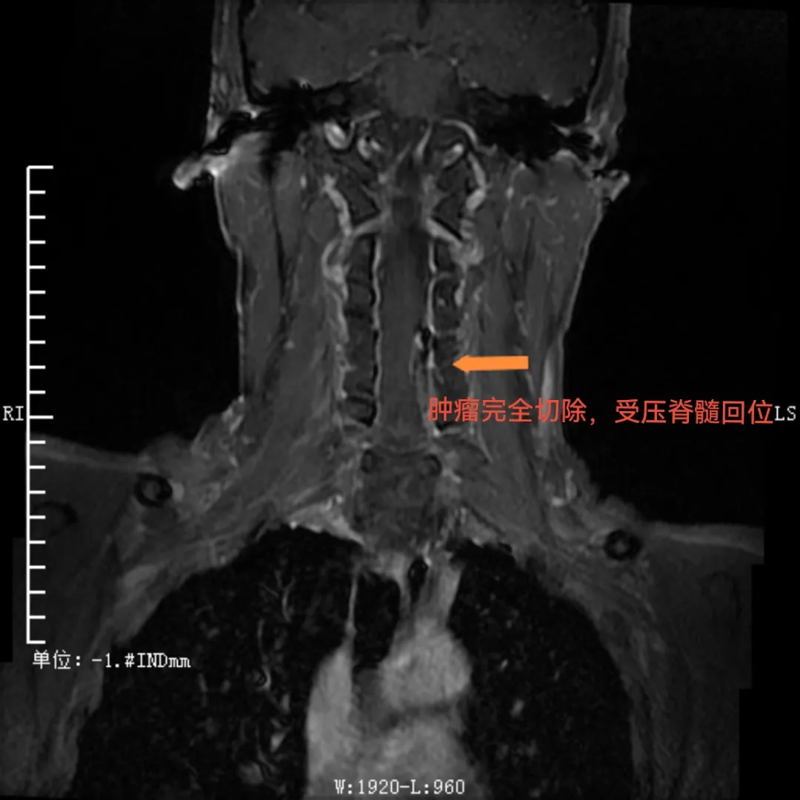

术后,肿瘤完全切除,受压脊髓回位

与传统手术需要完全切除肿瘤节段全椎板不同,这种新的手术方式术后仅需将掀起的椎板纳还并以丝线固定即可,无需使用金属连接耗材固定。这不仅使得复位效果更佳,而且患者在术后复查CT、磁共振时无金属伪影干扰,让检查结果诊断更准确,还为患者节省了相当大的一笔费用。